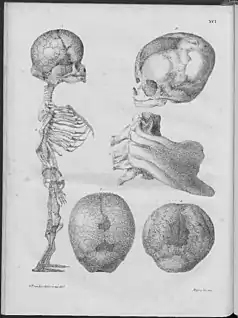

Willem Vrolik, a Dutch anatomist who was also curator of the "Museum Vrolikianum", which made him privy to many specimens of bodies having birth defects, coined the term "osteogenesis imperfecta"[27]: 683 in his bilingual Latin and Dutch language book on teratology, Illustrations of Human and Mammalian Embryogenesis, first published in 1849.[150]

Included is a description of the remains of an infant who had what is now known as perinatally fatal OI type II[3]: 347 [1]: 5 (as verified in a 1998 re-examination of the remains by Baljet et al.).[151] The remains were first given to Vrolik's father, who could not make sense of them. Vrolik described poorly mineralized bones, bowed long bones, and fractures in various states of healing.[152] Vrolik correctly determined that what he termed OI in the infant was not caused by secondary rickets, but a congenital abnormality causing primary osteopenia; he theorized this was due to a lack of "intrinsic generative energy".[151]